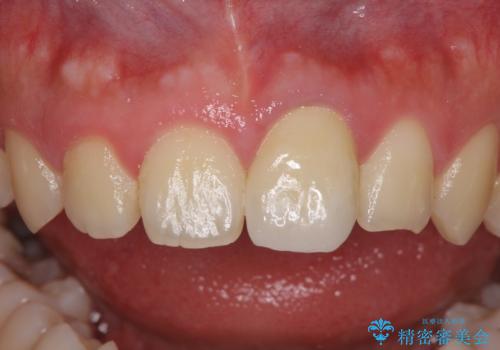

- 中学生の時にぶつけて以来、そのままにしていたところ前歯が変色してきたとのことで来院された患者様です。

レントゲン写真より、歯の中の神経組織が失活していることが分かったため、根管治療、ファイバーコアによる土台築製を行い、オーダーメイドタイプのオールセラミッククラウンにて補綴することとしました。